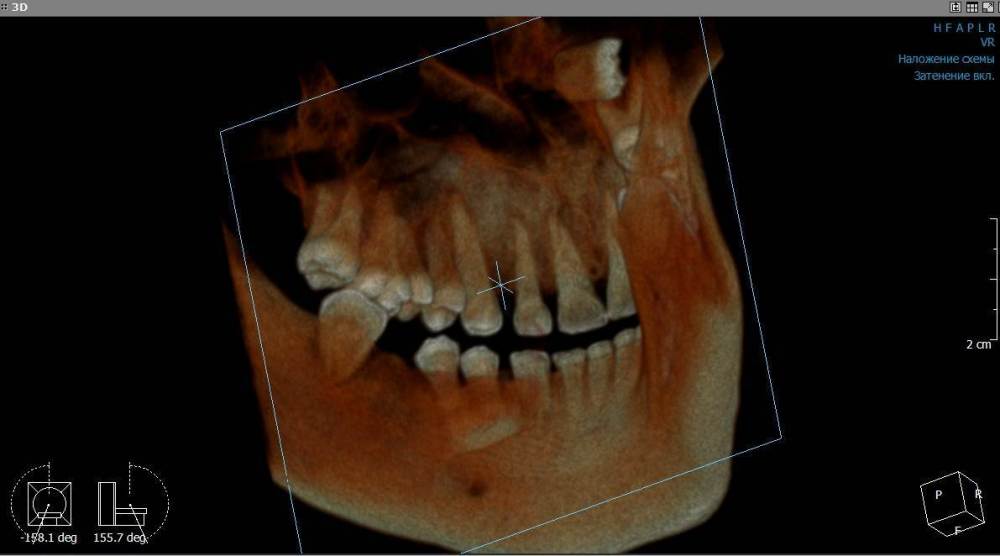

Mnrg Опубликовано 7 июля, 2023 Автор Поделиться Опубликовано 7 июля, 2023 6 минут назад, wladdX сказал: Гайморит у вас совершенно необязательно имеет одонтогенную природу (вызван зубами). Судя по КТ, зуб 16 может быть виновником (а может и не быть). Для уточнения нужна также проверка витальности его пульпы (жив нерв или нет). Если пульпа нежизнеспособна, то этот зуб почти наверняка поддерживает воспалительный процесс в пазухе. Зуб 18 вряд ли нужно трогать. Лежит он себе в кости и пускай, никому он там не вредит. Да он вплотную прилежит к корням зуба 17, но и только. С внешней средой не контактирует. Никакого негативного влияния на соседние зубы он оказывать не должен: формирование корней завершено, потенции к росту и какому-либо движению нет. Удаление зуба 18 в данной ситуации вряд ли оправдано. Процедура не самая простая, но и не запредельной сложности. Шестерку проверяли холодом - чувствует, не знаю, означает ли это жизнеспособность пульпы, но на холод реагировал немного сильней других зубов. Сегодня открыл КТ программой RadiAntViewer и обнаружил в 3D просмотре визуальные признаки нахождения части восьмерки в краю пазухи. Конечно я не могу утверждать, т.к не врач и насколько понимаю это режим моделирования, но все же выглядит убедительно на мой скромный взгляд. Еще один глупый вопрос, если позволите) Возможно ли в шестерке в одном из трех корней воспаление и нерв разрушен, а другие два при этом будут создавать чувствительность, т.е быть "живыми" или же это фантастика? Деньги запросили немалые для нашего региона за депульпацию (13к) поэтому пытаюсь собрать как можно больше информации прежде, чем принимать решения. Ссылка на комментарий